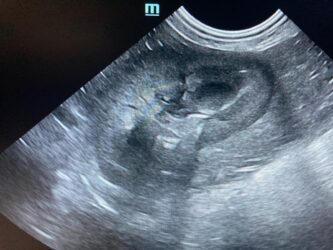

Dimitri, CV, 9.6kg, 11j, MC, bijgeruis 4/6 waarvoor hij vetmedin krijgt en opgevolgd wordt door cardioloog:

21/08/2025: Bij buurtcollega aangeboden voor hematurie. Plast vlot, op’t einde bloed te zien. Mevr. kookt zelf voor hem. Echo gehad + UOZ (geen idee hoe dit werd gecollecteerd) gedaan. Veel bloed in de…